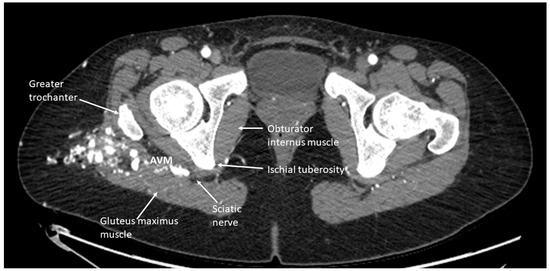

• When administering peripheral nerve blocks in pediatric patients, it is essential to consider potential complications from the nerve block and injecting the sclerosing/embolizing agents. The risk of nerve injury from nerve blocks is low, around 2 to 4 per 10,000 blocks in children, but it should still be considered in all patients undergoing this type of therapy [15]. One patient developed a sciatic nerve injury following therapy with a peripheral nerve block. The malformation was located in the hip and close to the sciatic nerve (Figure 5). A quadratus lumborum nerve block was performed intraoperatively for postoperative pain control [16]. The patient made a full neurologic recovery after several months. The nerve injury was likely due to the therapy and unrelated to the peripheral nerve block. However, determining if the malformation is close to a nerve should raise concerns that signs of a nerve injury may be initially masked by a peripheral nerve block. As previously reported for other blocks by Pickle et al. [17] encountered no bleeding complications at the block sites after enoxaparin administration. Continuous patient monitoring during and after the procedure is vital to ensure their safety. Close observation for potential complications related to the nerve block, such as nerve injury, is necessary. At the UPMC CHP, we performed home phone call follow-ups for all the patients who received peripheral nerve block follow-up. Some of our patients required pre- and post-procedure anticoagulation therapy, and we investigated if any of our patients developed any hematoma at the needle injection site. In addition, some patients require a longer time to recover from peripheral nerve blockade.

Figure 5. CT scan imaging of a right hip arteriovenous malformation with involvement close to the sciatic nerve. This patient had undergone several sclerotherapy procedures and received a quadratus lumborum nerve block for postoperative pain management. Following one therapy, the patient was noted to have a sciatic nerve injury.